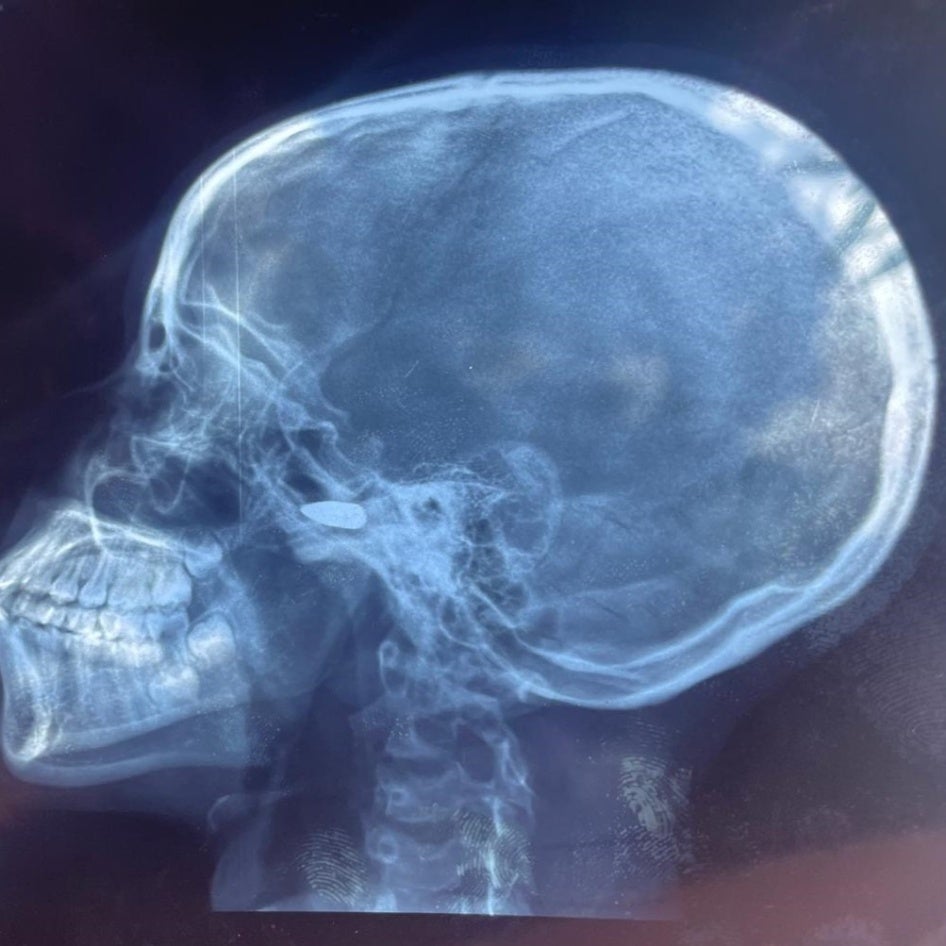

Das Röntgenbild eines 15-jährigen Mädchens, das am 9. Mai 2024 in Bébédja im Süden des Tschad von einem Querschläger in den Kopf getroffen wurde, nachdem die vorläufigen Ergebnisse der Präsidentschaftswahlen im Tschad bekannt gegeben worden waren. © 2024 Private

Am 9. Mai gaben die Behörden die vorläufigen Ergebnisse der drei Tage zuvor abgehaltenen Präsidentschaftswahlen bekannt. Sie erklärten den damaligen Übergangspräsidenten, General Mahamat Idriss Déby, zum Sieger. Die Sicherheitskräfte des Tschad, die Déby treu ergeben waren, feierten, indem sie in Städten und Dörfern um sich schossen.